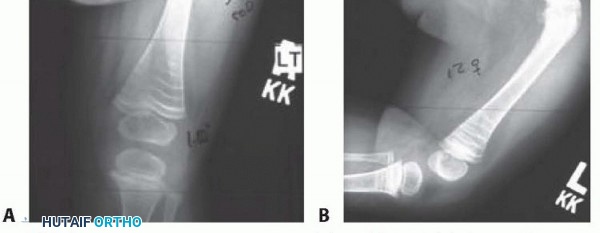

FIG 5 • Common severe anterior (A) and lateral (B) femoral bowing. This is apparent rather than true coxa vara.

## An incomplete osteotomy is performed while stability of the leg is maintained manually. The osteotomy is completed with gentle manual pressure, the guidewire is extended to the next osteotomy site, and the process is continued until all deformities are corrected. For severe deformities, an open segmental resection at the apex is necessary to avoid excessive soft tissue tension (see FIGS 2 and 5) on structures such as the sciatic nerve. Rarely are more than two osteotomies required.